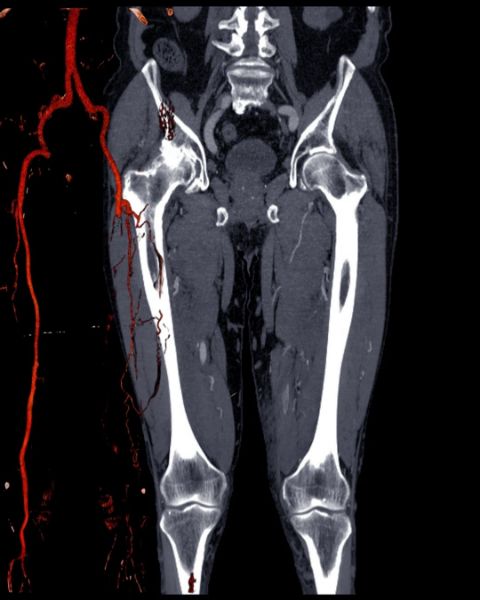

Bilateral: Her iki tarafı kapsar. Yani bu durumda hem sağ hem sol bacakları ifade eder. Alt Ekstremite: Bacaklar ve ayakları kapsayan tıbbi terimdir. MR (Manyetik Rezonans): Vücutta manyetik alan ve radyo dalgaları kullanarak detaylı görüntü elde eden bir görüntüleme yöntemidir. Röntgen veya CT gibi radyasyon içermez. Anjiyo: Damarların (arter veya ven) görüntülenmesidir. MR Anjiyo’da kontrast maddesi kullanılarak damar yapıları detaylı şekilde incelenir.

Bilateral Alt Ekstremite MR Anjiyo, her iki bacaktaki damarların (atar ve toplardamarların) manyetik rezonans ile detaylı olarak görüntülenmesidir.

• Genellikle damar tıkanıklığı, daralma, pıhtı, varis veya anevrizma şüphesi olduğunda yapılır.

• Non-invaziv bir yöntemdir, yani cerrahi müdahale gerektirmez.

• Gerekirse kontrast maddesi ile damarlar daha net görülebilir.